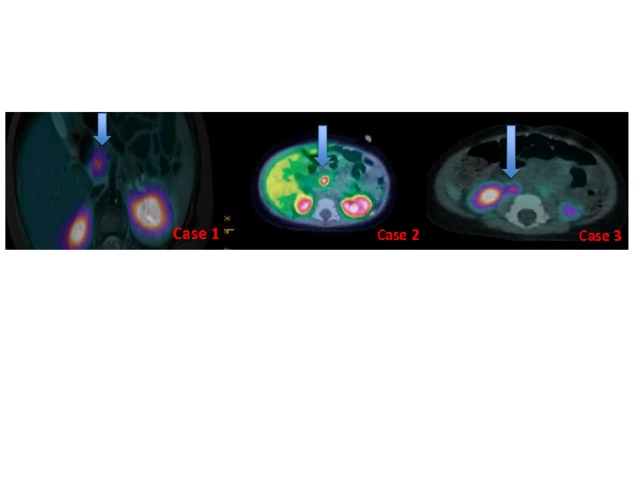

BACKGROUND: A long-acting somatostatin analogue (lanreotide) is used in the management of a diazoxide-unresponsive diffuse form of congenital hyperinsulinism (CHI). However, no reports of its use in patients with the focal form of CHI exist. Case 1: A 1-month-old boy diagnosed with diazoxide-unresponsive CHI due to a paternal heterozygous ABCC8 gene mutation showed partial response to octreotide. 18F-DOPA-PET/CT scan revealed a focal lesion in the pancreatic head. Surgical removal of the lesion was unsuccessful. He was switched to monthly lanreotide treatment at the age of 11 months, which stabilised his blood glucose over a 12-month period. Case 2: A 1-month-old boy with diazoxide-unresponsive CHI due to a paternal heterozygous KCNJ11 gene mutation was partially responsive to octreotide. 18F-DOPA-PET/CT scan confirmed a focal pancreatic head lesion. Over 6 months, he underwent 3 lesionectomies and afterwards responded to octreotide. At the age of 9 months, treatment was switched to monthly lanreotide. Currently, he is aged 3, with stable glycaemia, and improved fasting tolerance. Case 3: A 3-week-old girl with a paternal heterozygous ABCC8 gene mutation was unresponsive to diazoxide. 18F-DOPA-PET/CT scan confirmed a focal pancreatic head lesion. She responded to octreotide, and her parents preferred to avoid pancreatic surgery. At the age of 20 months, treatment was switched to monthly lanreotide, resulting in euglycaemia over the last 7 months. CONCLUSION: CHI patients with focal pancreatic head lesions are challenging, especially if not surgically amenable. Conservative treatment is preferable, and lanreotide might be an option. The therapeutic impact of lanreotide treatment in patients with the focal forms of CHI should be confirmed in prospective studies with close monitoring of the side effects.